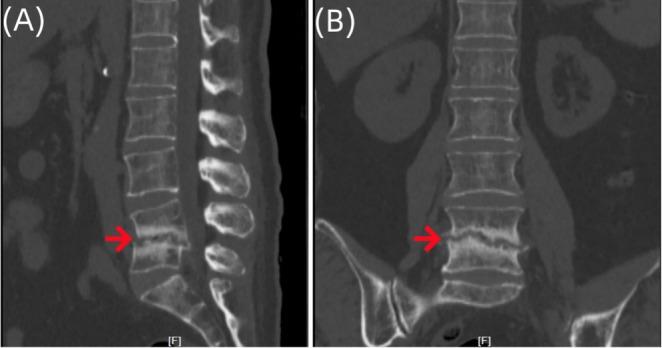

Suppurative Spondylitis Misdiagnosed as Endplate Inflammation: A Rare Case Report.

Spinal infectious diseases are difficult to diagnose and treat; we reported a case of pyogenic spondylitis misdiagnosed as terminal discitis and successfully treated. The application of metagenomic next-generation sequencing technology holds promise in greatly improving diagnostic efficiency.